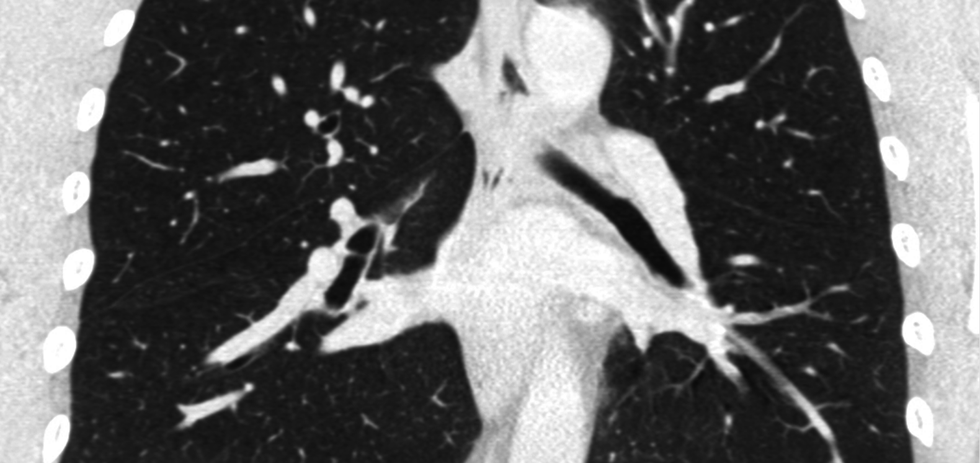

Volumetric is banking on their technology being among the inventions that will lead the medical industry into the future. The human tissue-printing technology company has created the 3D printer and the "ink" that can create whole organs for transplant.

"We can create complicated vascular architectures inside of soft water-based gels, in this case, mimicking the structure and function of human lung tissue," says Jordan Miller, CEO. "We can oxygenate red blood cells."